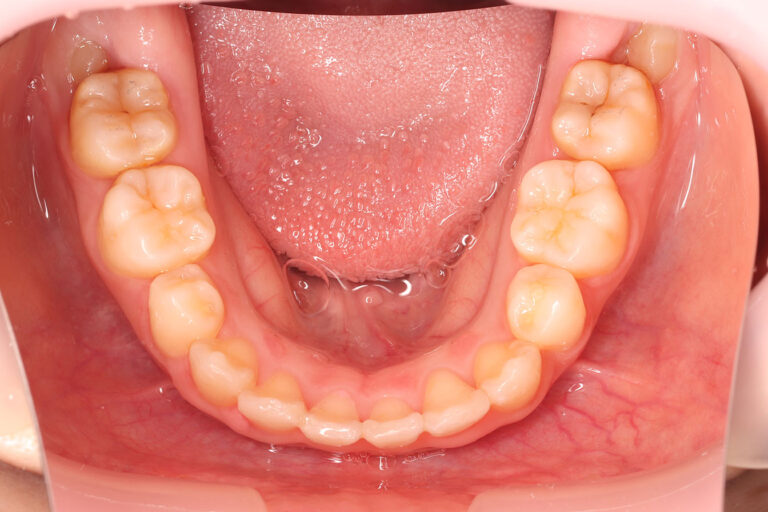

| 上下顎の歯列全体に重度の叢生(がたつき・八重歯)がある患者さんです。

正中は上下とも右側に大きくずれています。前歯は上下とも内側(舌側)に押し込まれています。 特に、上顎犬歯ですが、右側は外側(頬側)に飛び出していますが、左側は内側(舌側)に入っています。 ガタガタの歯並びが昔から気になっていたということで永久歯列からのマルチブラケット装置(本格矯正)での動的治療を開始しました。 マルチブラケット 動的治療期間 3年0か月 調整回数27回 叢生が非常に強く、舌側転位している上顎左側犬歯の改善に5か月ほど追加で時間を費やしました。 重度の叢生は改善され、歯列正中も左側に移動させ改善しています。 口元はもともと良好でしたので、治療前後の口唇の位置、口元の状態は大きく変えずに治療を終了しています。 装置撤去後の保定期間に、一番後ろから生えてきた親知らず(第三大臼歯)は抜歯してもらう予定です。(治療した歯並びが長持ちするように。) | ||